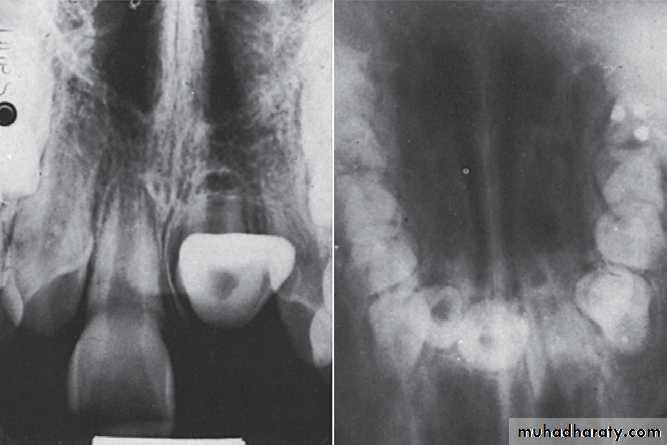

A, Pulp of the fi rst permanent molar was exposed by caries. The tooth was considered a candidate for the calcium hydroxide pulpotomy technique.

B, Calcifi ed

bridge has formed over the vital pulp in the canals.C, Continued

root development and pulpal recession are indicative of continuing pulpal vitality. The crown should be supported with a full-coverage restoration.Mature and immature teeth in the x-ray

Closed apex maxillary central incisors (mature)Open apex maxillary central incisors (immature)